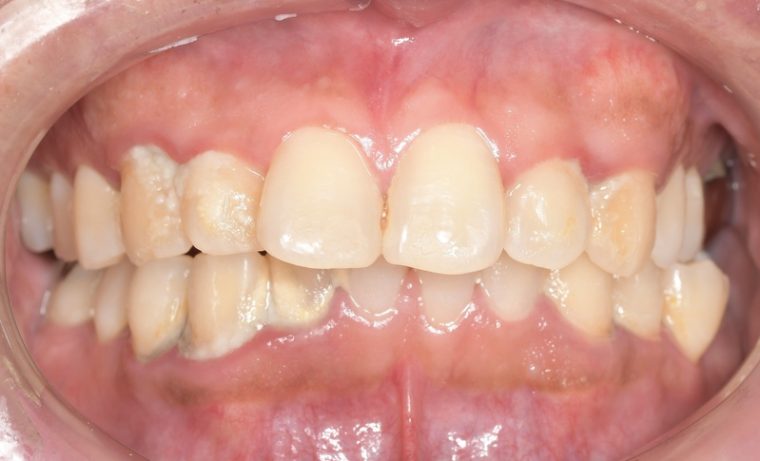

症例5

before

症例

after

歯周病検査(治療前)

歯周病検査(治療後)

レントゲン写真

基本情報

年齢・性別 32歳・男性

主訴 主訴:歯ぐきから出血する

治療部位:全顎

治療内容 「全顎」

歯周基本治療(歯周精密検査、スケーリング、OHI、SRP)

治療期間 約3ヶ月

治療費 歯周基本検査:約600円(保険診療3割負担)

スケーリング、OHI:約2,000円(保険診療3割負担)×2回

SRP、OHI:約1,500円(保険診療3割負担)×4回

歯周精密検査:約1,200円(保険診療3割負担)×2回

合計金額13,000円

(2025年2月現在)

リスク・副作用 歯石を取った後に、歯がしみることがあります。

治療方針 ①検査

レントゲン、口腔内写真を撮影して、歯や歯周組織の状態を確認します。

また、歯周病の検査で歯周ポケットの深さや出血の有無を確認します。

②スケーリング、OHI(口腔衛生指導)

スケーリングをして歯の表面の歯石を除去します。

また、正しい歯磨きの仕方や、フロスの通し方を一緒に確認します。

③歯周精密検査

前回歯石除去と歯磨き指導を行なった結果、歯ぐきの状態がどれぐらい改善したか検査します。

④SRP

歯ぐきの内側についてる歯石を除去します。

⑤歯周精密検査

SRP後、歯周病が改善されたか、検査します。

歯周ポケットが4ミリ以上の部位は、再度SRPを行います。

今回は歯周病の状態が安定したため、3ヶ月おきの定期検診で歯周病の再発や進行を防ぎます。

特記事項 歯周精密検査について:

・歯周ポケットが4ミリ以上ある場合は歯周病で、3ミリ以下は健康な歯ぐきです。

・出血の有無で炎症があるか確認します。

・磨き残しがある部分を確認して記録します。

担当者所見 初診時は、写真を見て分かるように、歯ぐきが赤く腫れていました。

また、歯周病の検査では、全体的に歯と歯の間の部分の歯周ポケットが4ミリあり、全体の約81%から出血が認められました。

出血量も多く、歯ぐきに触れた瞬間に出血しました。

レントゲンで骨のレベルがしっかりとあることが確認できました。

そのため、ご自身で正しい歯磨きを継続することで改善すると考えました。

歯周基本治療を経て、再度検査した結果、歯周ポケットはほぼ3ミリ以下に改善しました。左下7番の残存した歯周ポケットは、隣の親知らずを抜いたため経過観察します。

出血率は約4%まで改善し、出血量も点状で少なくなりました。

今後は右上2番、右下3番の歯ぐきの発赤の改善と、出血率0%を目指して、定期検診でメンテナンスしていきます。